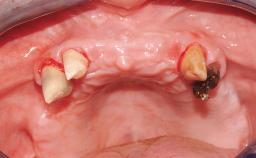

Immediate Loading of Eight Implants in the Maxilla and Six Implants in the Mandible and Final Restoration with Three-Unit and Four-Unit FDPs

Case Type Edentulous Maxilla

Defining Characteristics Fully edentulous upper jaw to be rehabilitated with four or more implants

Defining Characteristics Fully edentulous upper jaw to be rehabilitated with an implant-borne fixed dental prosthesis